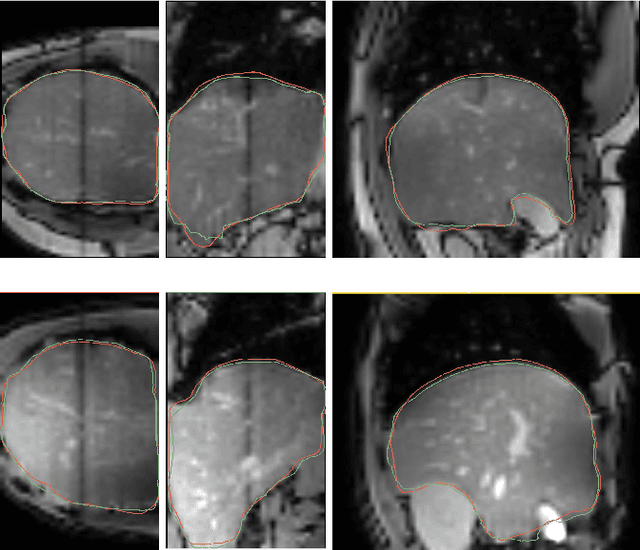

Abstract:Intensity modulated radiotherapy (IMRT) is one of the most common modalities for treating cancer patients. One of the biggest challenges is precise treatment delivery that accounts for varying motion patterns originating from free-breathing. Currently, image-guided solutions for IMRT is limited to 2D guidance due to the complexity of 3D tracking solutions. We propose a novel end-to-end attention graph neural network model that generates in real-time a triangular shape of the liver based on a reference segmentation obtained at the preoperative phase and a 2D MRI coronal slice taken during the treatment. Graph neural networks work directly with graph data and can capture hidden patterns in non-Euclidean domains. Furthermore, contrary to existing methods, it produces the shape entirely in a mesh structure and correctly infers mesh shape and position based on a surrogate image. We define two on-the-fly approaches to make the correspondence of liver mesh vertices with 2D images obtained during treatment. Furthermore, we introduce a novel task-specific identity loss to constrain the deformation of the liver in the graph neural network to limit phenomenons such as flying vertices or mesh holes. The proposed method achieves results with an average error of 3.06 +- 0.7 mm and Chamfer distance with L2 norm of 63.14 +- 27.28.